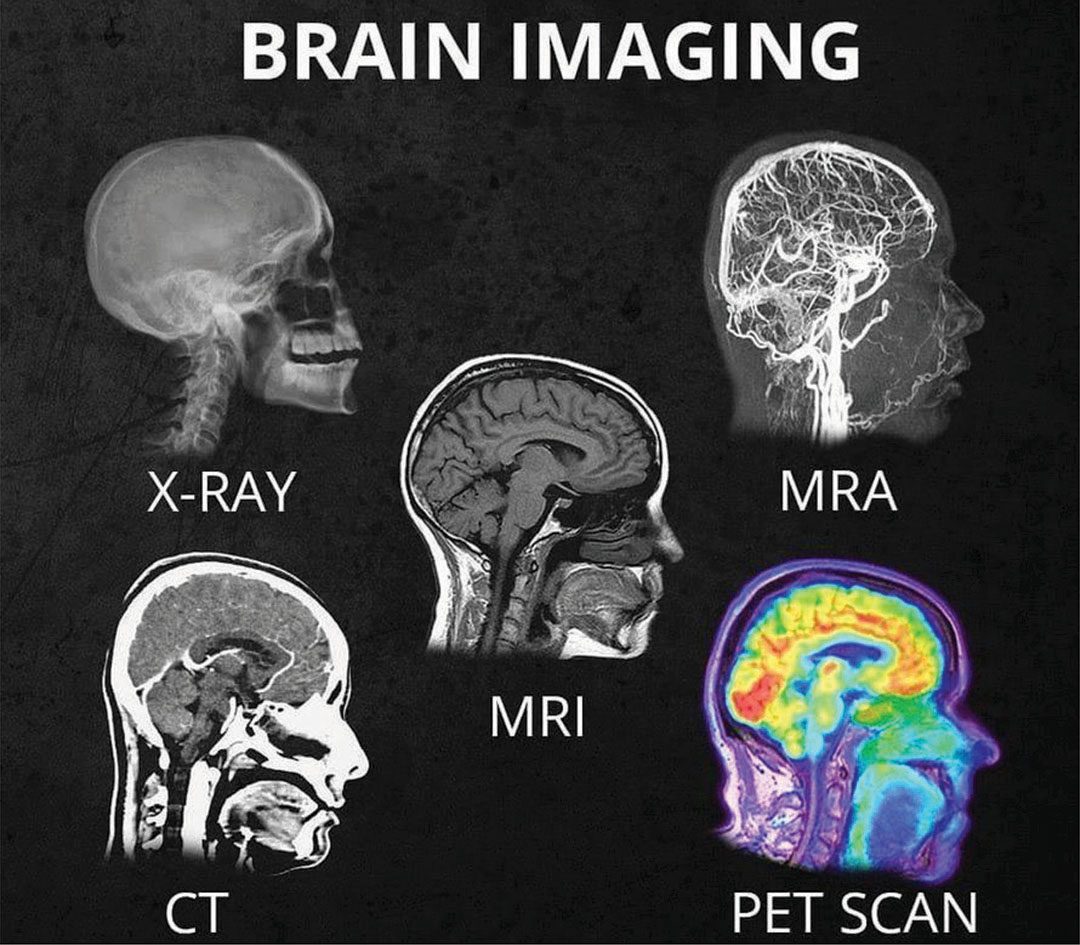

Brain Scans: Technologies That Peer Inside Your Head

www.brainfacts.org

www.brainfacts.org

scans mri

X-ray Archives - San Diego Brain Injury Foundation

sdbif.org

sdbif.org